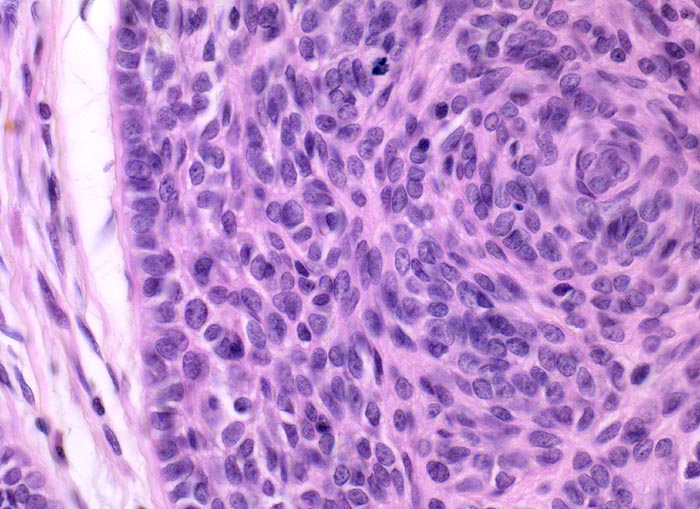

• Solide blaue Tumorzellplatten in der Dermis, teils mit Kontakt zur Epidermis.

• Die zytoplasmaarmen Tumorzellen ähneln Basalzellen der Epidermis.

• Palisadenförmige Anordnung der Tumorzellen am Rand der Zellplatten.

• Retraktionsartefakt zwischen Tumor und Stroma.